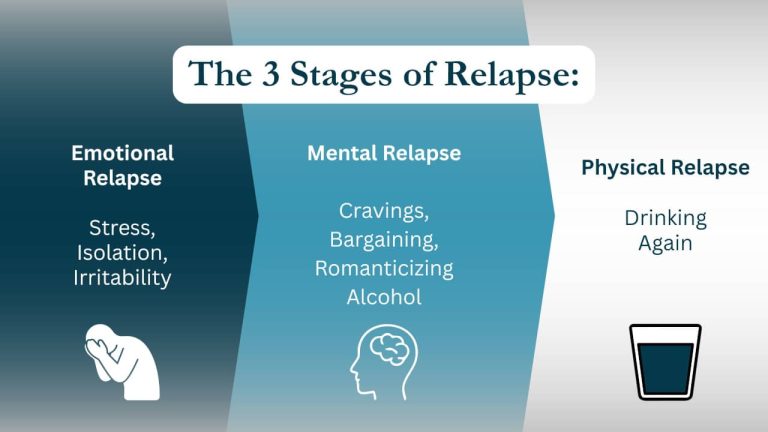

Addiction often coexists with emotional and psychological issues, such as anxiety, depression, trauma, and unresolved emotional pain. The journey toward healing requires more than abstaining from substances; it involves addressing these coexisting mental health issues that are often both causes and consequences of addiction.

One of the most significant aspects of recovery is emotional healing, which involves processing the emotional pain, guilt, and shame often carried by those with addiction. Emotions are closely linked to addictive behavior, with individuals turning to substances as a way to cope with overwhelming feelings. In recovery, it’s crucial to break this cycle by learning to manage emotions in healthy, constructive ways. Emotional healing focuses on improving self-awareness, emotional regulation, and developing positive coping mechanisms.